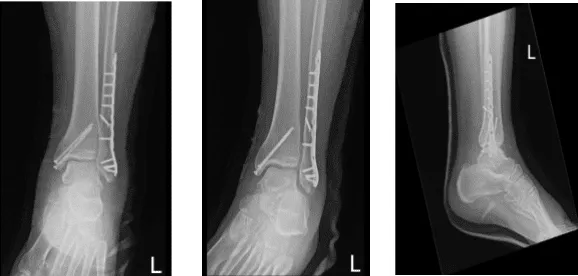

Ya se habían administrado antibióticos preoperatorios. Se realizó una incisión lateral centrada sobre la fractura. La fractura fue abierta y lavada. La fractura fue reducida y fijada con el tornillo interfragmentario insertado. Se aplicó una placa de neutralización sobre la maléola lateral, con los tornillos distal y proximal con una combinación de tornillos de bloqueo y no bloqueo que la encontraron en una posición aceptable.

Se tomaron y guardaron fotos. Ahora, la atención se desvió hacia el maléolo medial. Se hizo una incisión con palo de hockey a lo largo del maléolo medial. Se alcanzó el lugar de la fractura y estaba limpio. Había un periosteo que entraba en los sitios de fractura, que fue extirpado con una cuchilla.

La fractura fue abierta y lavada con líquido de irrigación. La fractura fue reducida y sujetada con una pinza. Los dos alambres guía se insertaron anterior y posterior a la pinza y la fractura se mantuvo en su lugar.

Se realizó una malleola medial e insertaron dos tornillos malleolares de 60 mm sobre los alambres guía. El ajuste final se realizó tras retirar los cables guía. Se tomaron fotos que se encontraron en posiciones aceptables. Las fotos se salvaron.

Radiografía completa del tobillo izquierdo 3 o más vistas